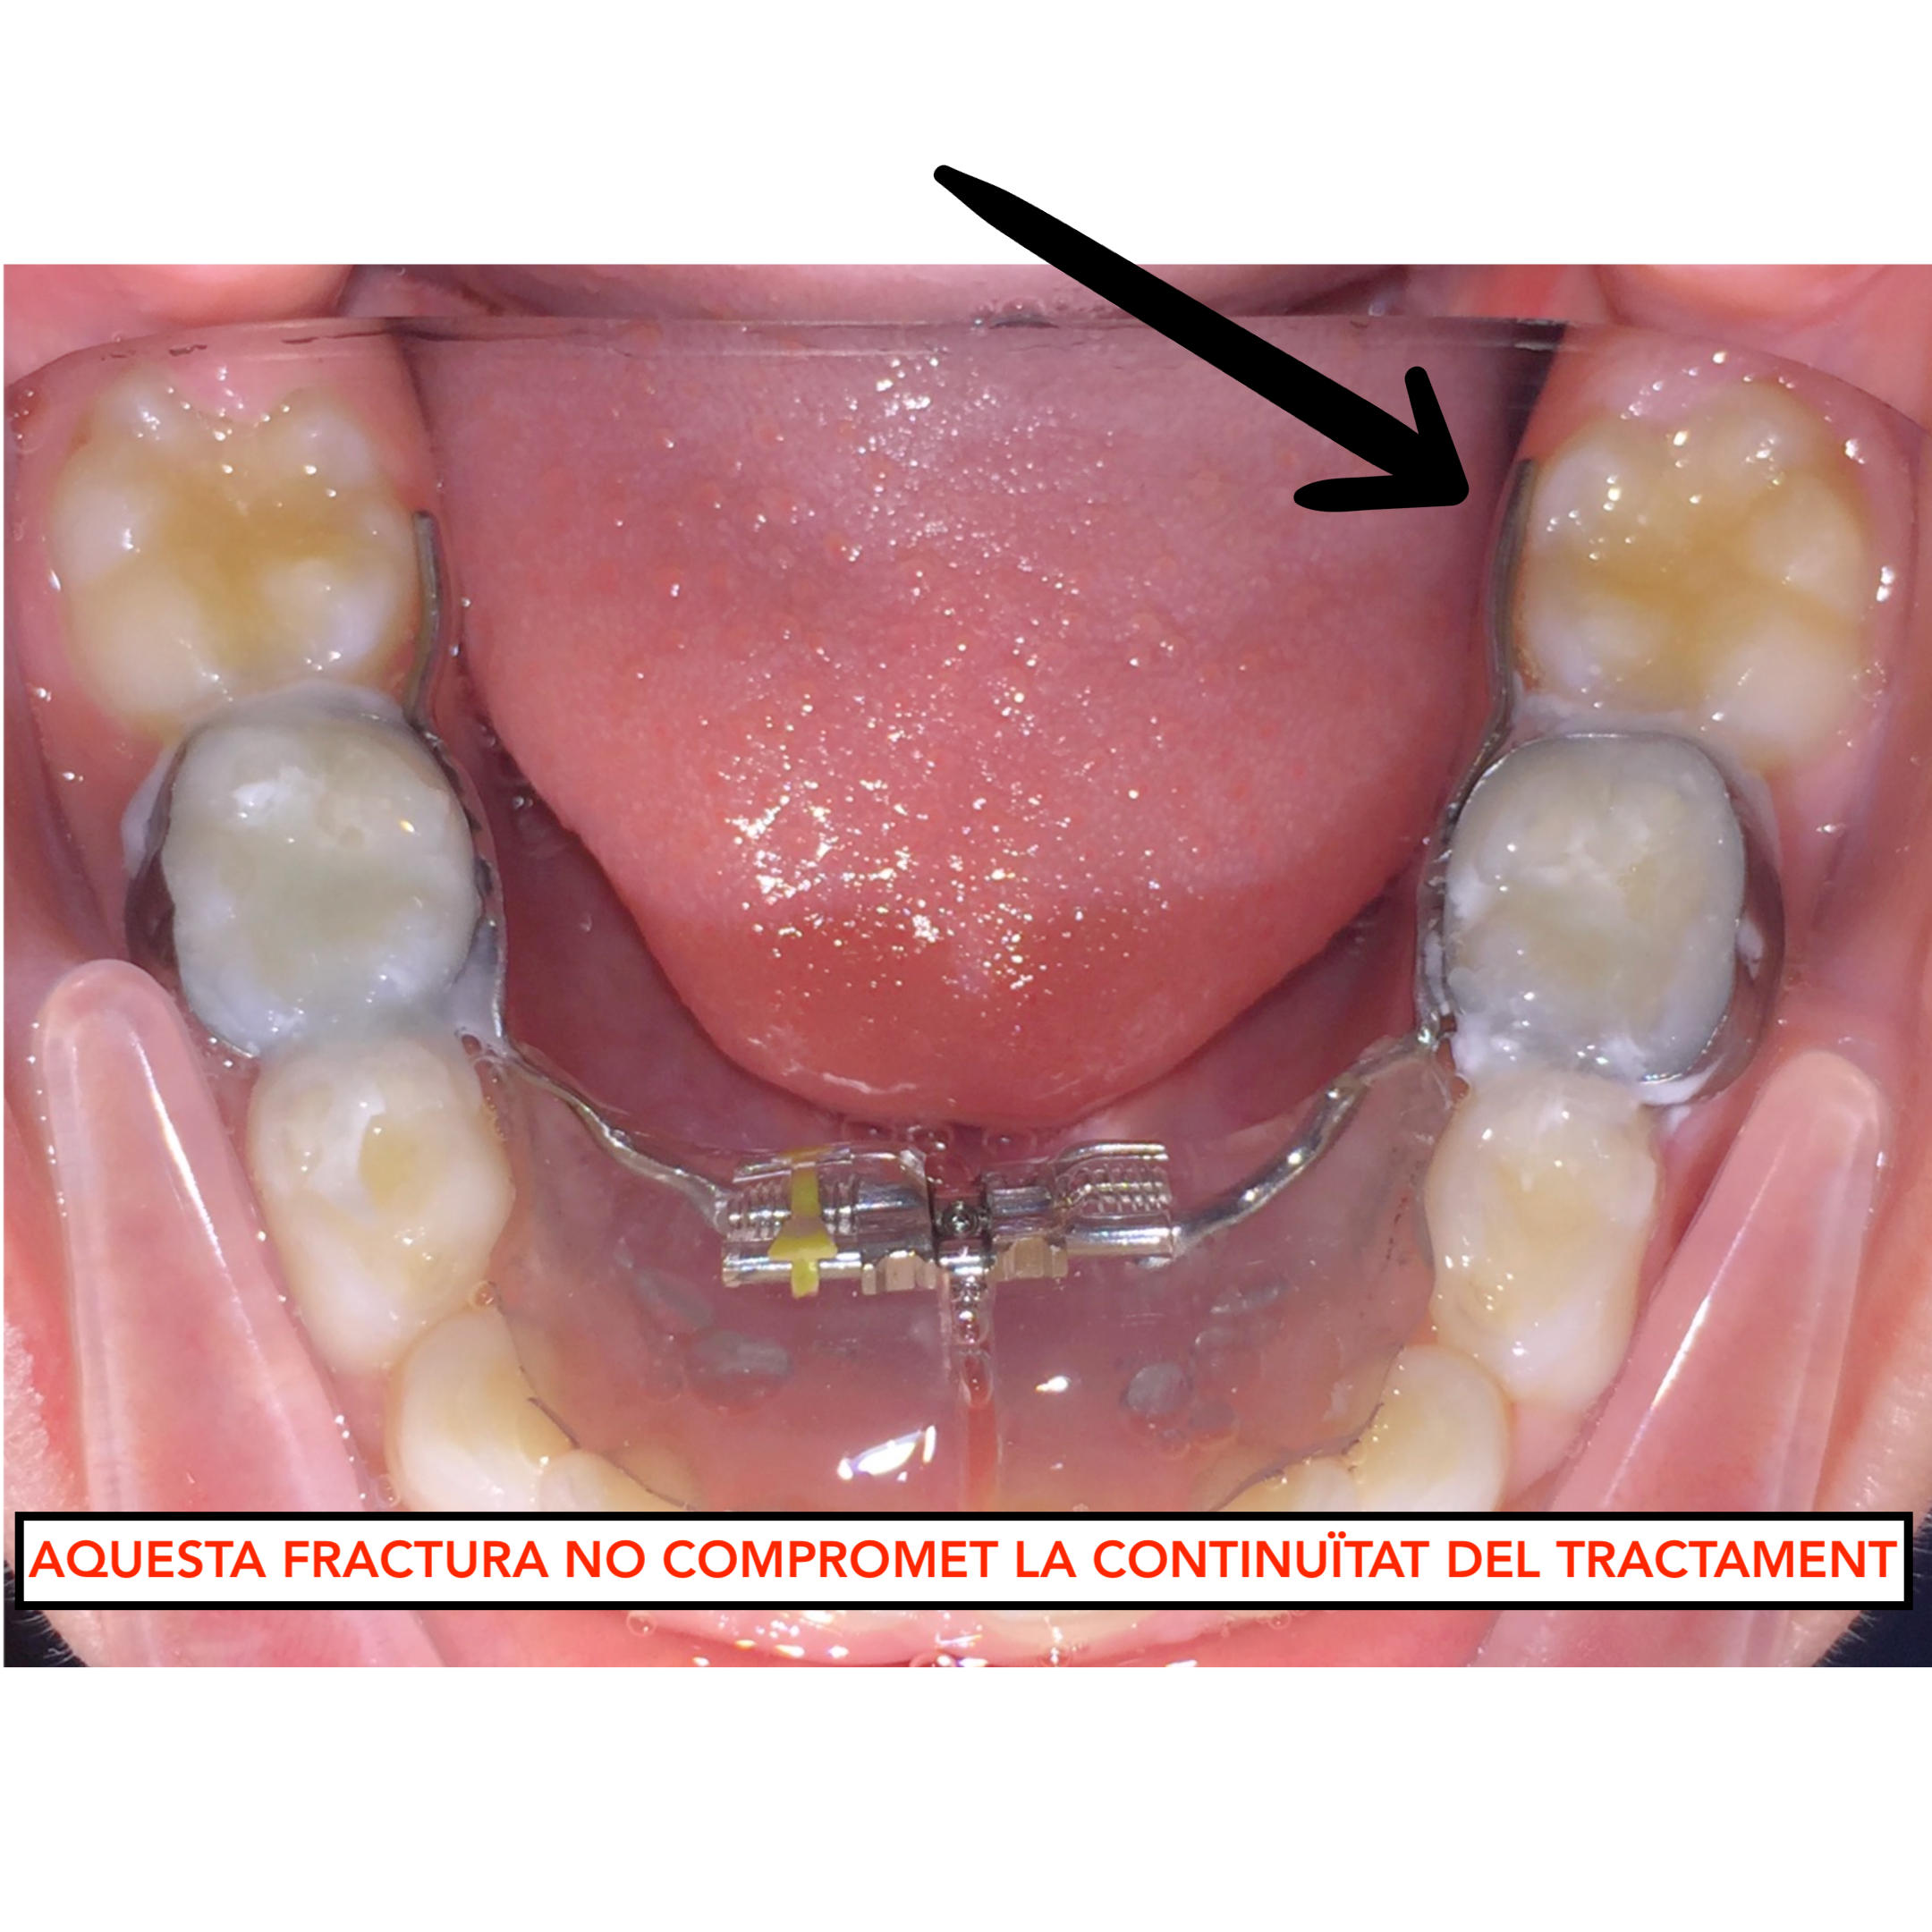

5. Fractura de l’aparell

Els aparells estan fabricats en un laboratori de plena confiança i amb materials d’alta qualitat. No obstant, estan sotmesos a forces masticatòries i d’altres tipus i en ocasions es poden fracturar.

Hi ha fractures que comprometen la continuïtat del tractament i d’altres no.

– Si detecteu alguna fractura de l’aparell –> envieu-nos un email + foto de l’aparell a: pacients@ipocubric.com

Aparell correcte

Aparell trencat